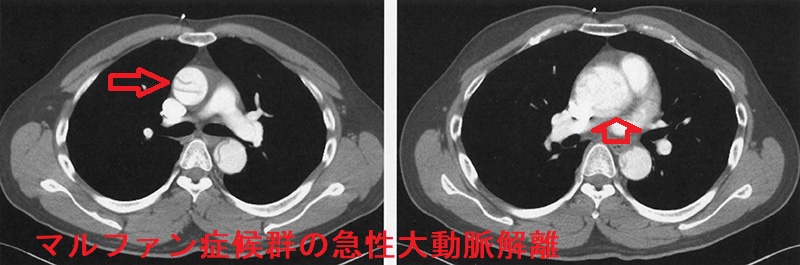

マルファン症候群の急性大動脈解離 胸部造影CT 水平断像;矢印はflap